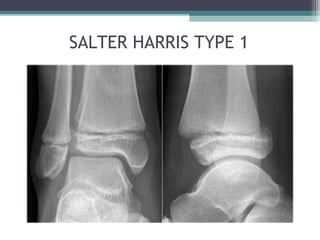

• SALTER-HARRIS (1963) – MOST WIDELY USED:

▫ TYPE 1: TRANVERSE FRACTURE IN HYPERTROPHIC ZONE

SALTER HARRIS TYPE 1